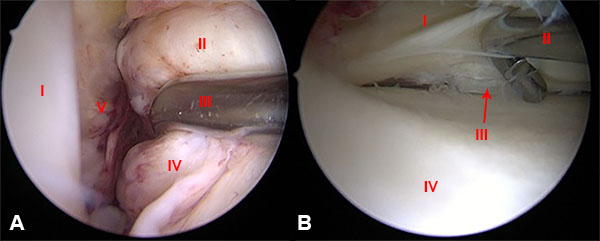

Con la paciente en posición supina en la mesa de operaciones y después de la inducción de la anestesia general, se realizó un examen bilateral de rodilla para observar y evaluar anomalías en comparación con el lado no lesionado. Se colocó el torniquete neumático bien acolchado y proximal en el muslo a operar con la rodilla a 90° de flexión con un soporte de pie para permitir un rango completo de movimiento y mayor comodidad para facilitar el procedimiento. El primer paso fue realizar una evaluación artroscópica estándar de la rodilla. Utilizamos un portal parapatelar lateral alto estándar para el artroscopio y un portal parapatelar medial para el instrumental. Se recomienda la colocación de una cánula maleable PassPort (Arthrex, Naples, FL) en el portal anteromedial para maximizar la visibilidad y el manejo de la sutura dentro y fuera del espacio de trabajo artroscópico. En este caso se detectó una lesión completa grado I del LCA con buena longitud y calidad de tejido del remanente (fig. 3A) y una lesión vertical longitudinal periférica del cuerno posterior del menisco interno (fig. 3B).

Figura 3: A) Imagen artroscópica de rodilla derecha, vista desde el portal anterolateral, con el paciente en posición supina y la rodilla a 90° de flexión que muestra la lesión tipo I del LCA. I: Cóndilo Femoral Externo. II: Remanente del LCA. III: Palpador. IV: LCA. V: Pared Medial. B) Imagen artroscópica, vista desde el portal anteromedial que muestra la lesión vertical circunferencial periférica del cuerno posterior del menisco interno. I: Cuerno Post. Menisco Int. II: Palpador. III: Lesión Vertical Longitudinal. IV: Meseta Tibial Interna.

En un primer tiempo se realizó la reparación del cuerno posterior del menisco interno. Para obtener un acceso con mejor visión y mas seguro realizamos la técnica de pie-crust sobre el LCM. Se preparan con shaver los bordes de la lesión, para mejorar el potencial de cicatrización.29 Luego se realiza la sutura meniscal fuera-adentro, con 3 puntos verticales ubicados cada 3 a 5 mm, utilizando aguja espinal de (18 gauge) precargada con sutura no absorbible, polidioxanona número 1 (PDS) a través de un portal postero medial estándar que se creó bajo la visualización artroscópica directa de la cápsula posteromedial. Logrando de esta forma la reducción anatómica y compresión circunferencial del menisco (fig. 4).